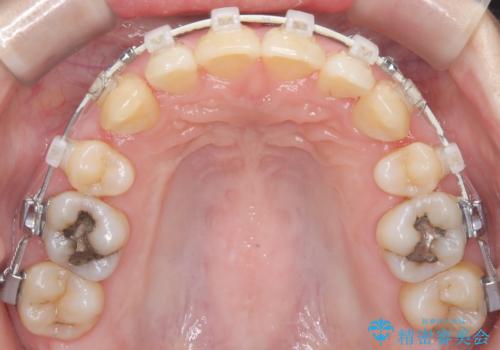

- 前歯の凸凹と前突感を改善するため、上下左右の4番を抜歯し、空いたスペースを利用して前歯を後方へ下げる審美ワイヤー矯正を計画しました。抜歯後は透明で目立ちにくい審美ブラケットを装着し、ワイヤーを用いて徐々に歯列を整えます。毎月1回の調整を通じて歯並びの変化を確認しながら、丁寧に矯正を進め、約2年で理想的な歯列と噛み合わせを完成させることを目指します。

前歯が前に出ていることや歯並びの凸凹が気になるという主訴でした。十分なスペースを確保するため上下左右の第一小臼歯(4番)を抜歯し、そこに前歯を移動させて整列を行いました。矯正装置には目立ちにくい透明なブラケットを選択し、見た目のストレスを軽減。矯正期間中は定期的な通院でワイヤーを微調整し、無理なく確実に歯を動かしました。治療後は前歯が自然な位置に下がり、口元の突出感が解消されるとともに、美しく整った口元に仕上がり、患者様にも大変喜んでいただけました。